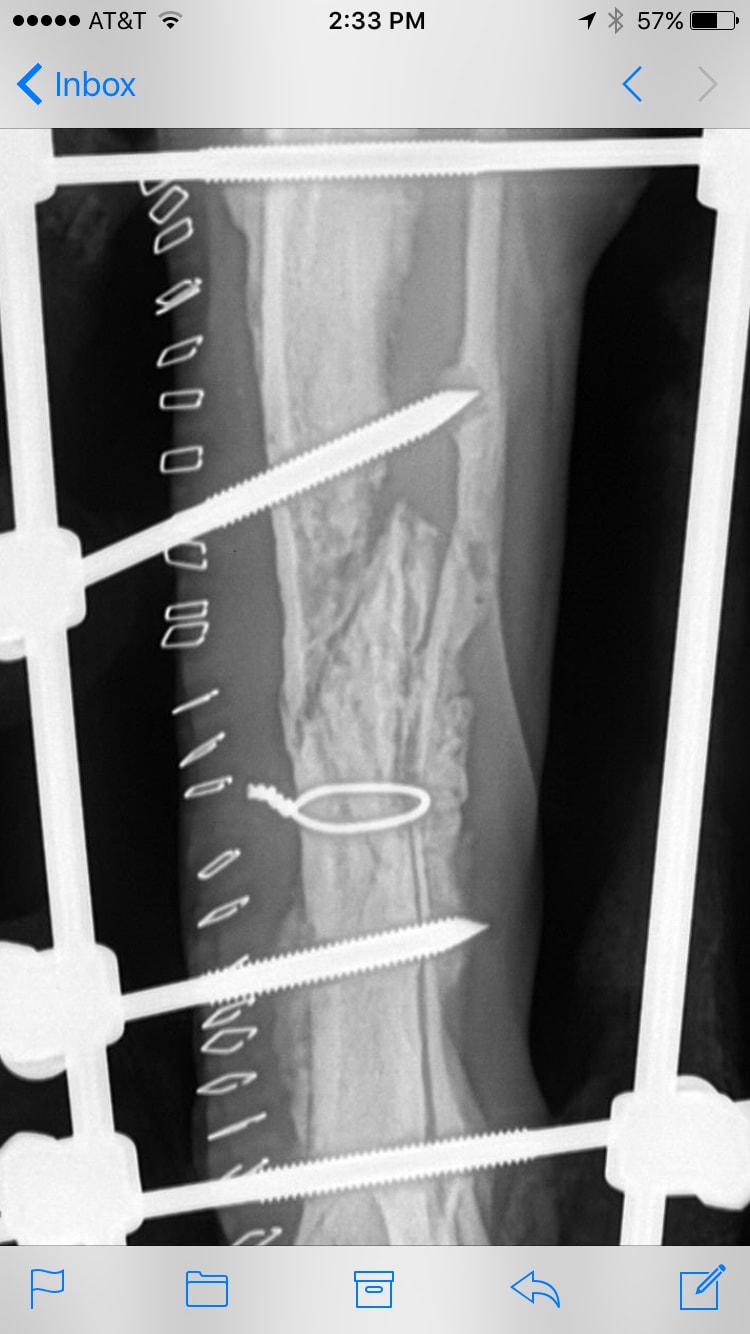

My 1.5 year old dog broke his back leg 23 days ago. We had an external fixator put in/on under the advice of our orthopedic vet. So far, our vet doesn't explain things clearly. All he would tell me is that it's not healing as quickly as he had hoped but to just keep him as still as possible and hope for the beat. Should I get a 2nd opinion? The surgery was $3k so I can't spend any more than I already have if he's right. I'm desparate to heal my baby quickly and safely.

3weeks is quite a short recovery time, there is some evidence of early callous around the fracture but this is still poorly organized. I would also recommend further rest and repeat xrays regularly up until 6weeks before any further intervention is considered. Cage rest should be planned